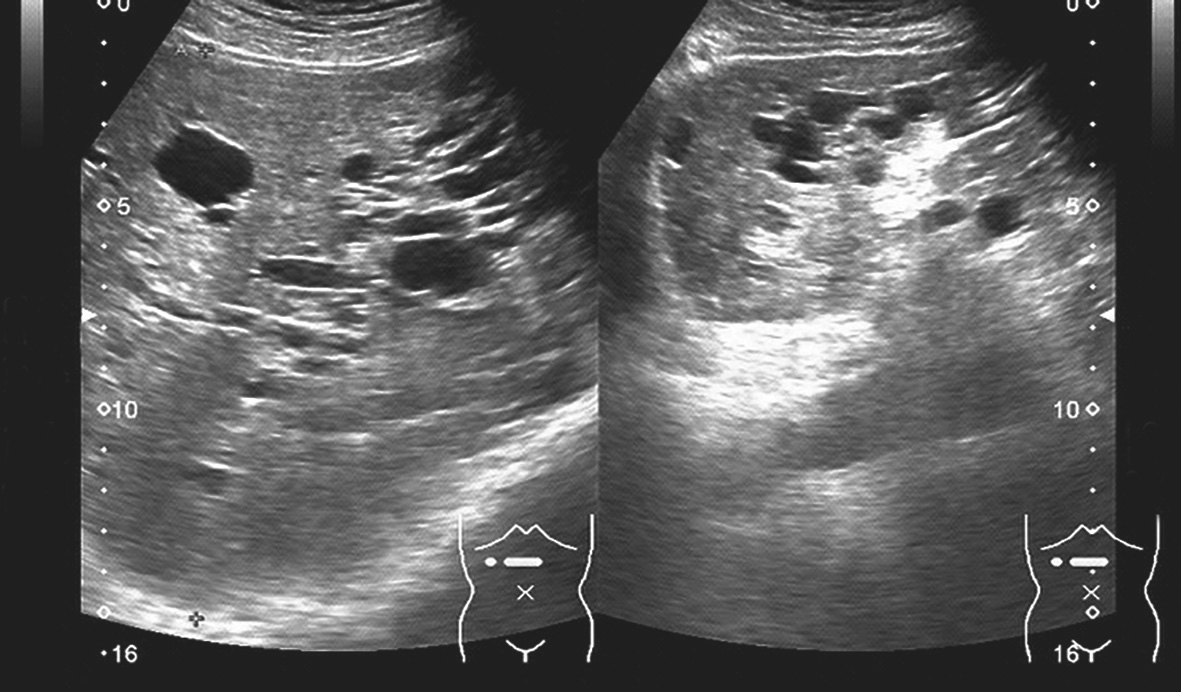

(2)囊肿大小不一,形态不一,内部透声好,后方回声增强可不明显,囊肿之间肝组织因纤维化改变回声可增强(图1-10-1、图1-10-2)。

图1-10-1 先天性多囊肝灰阶超声图像

图1-10-2 先天性多囊肝灰阶超声图像